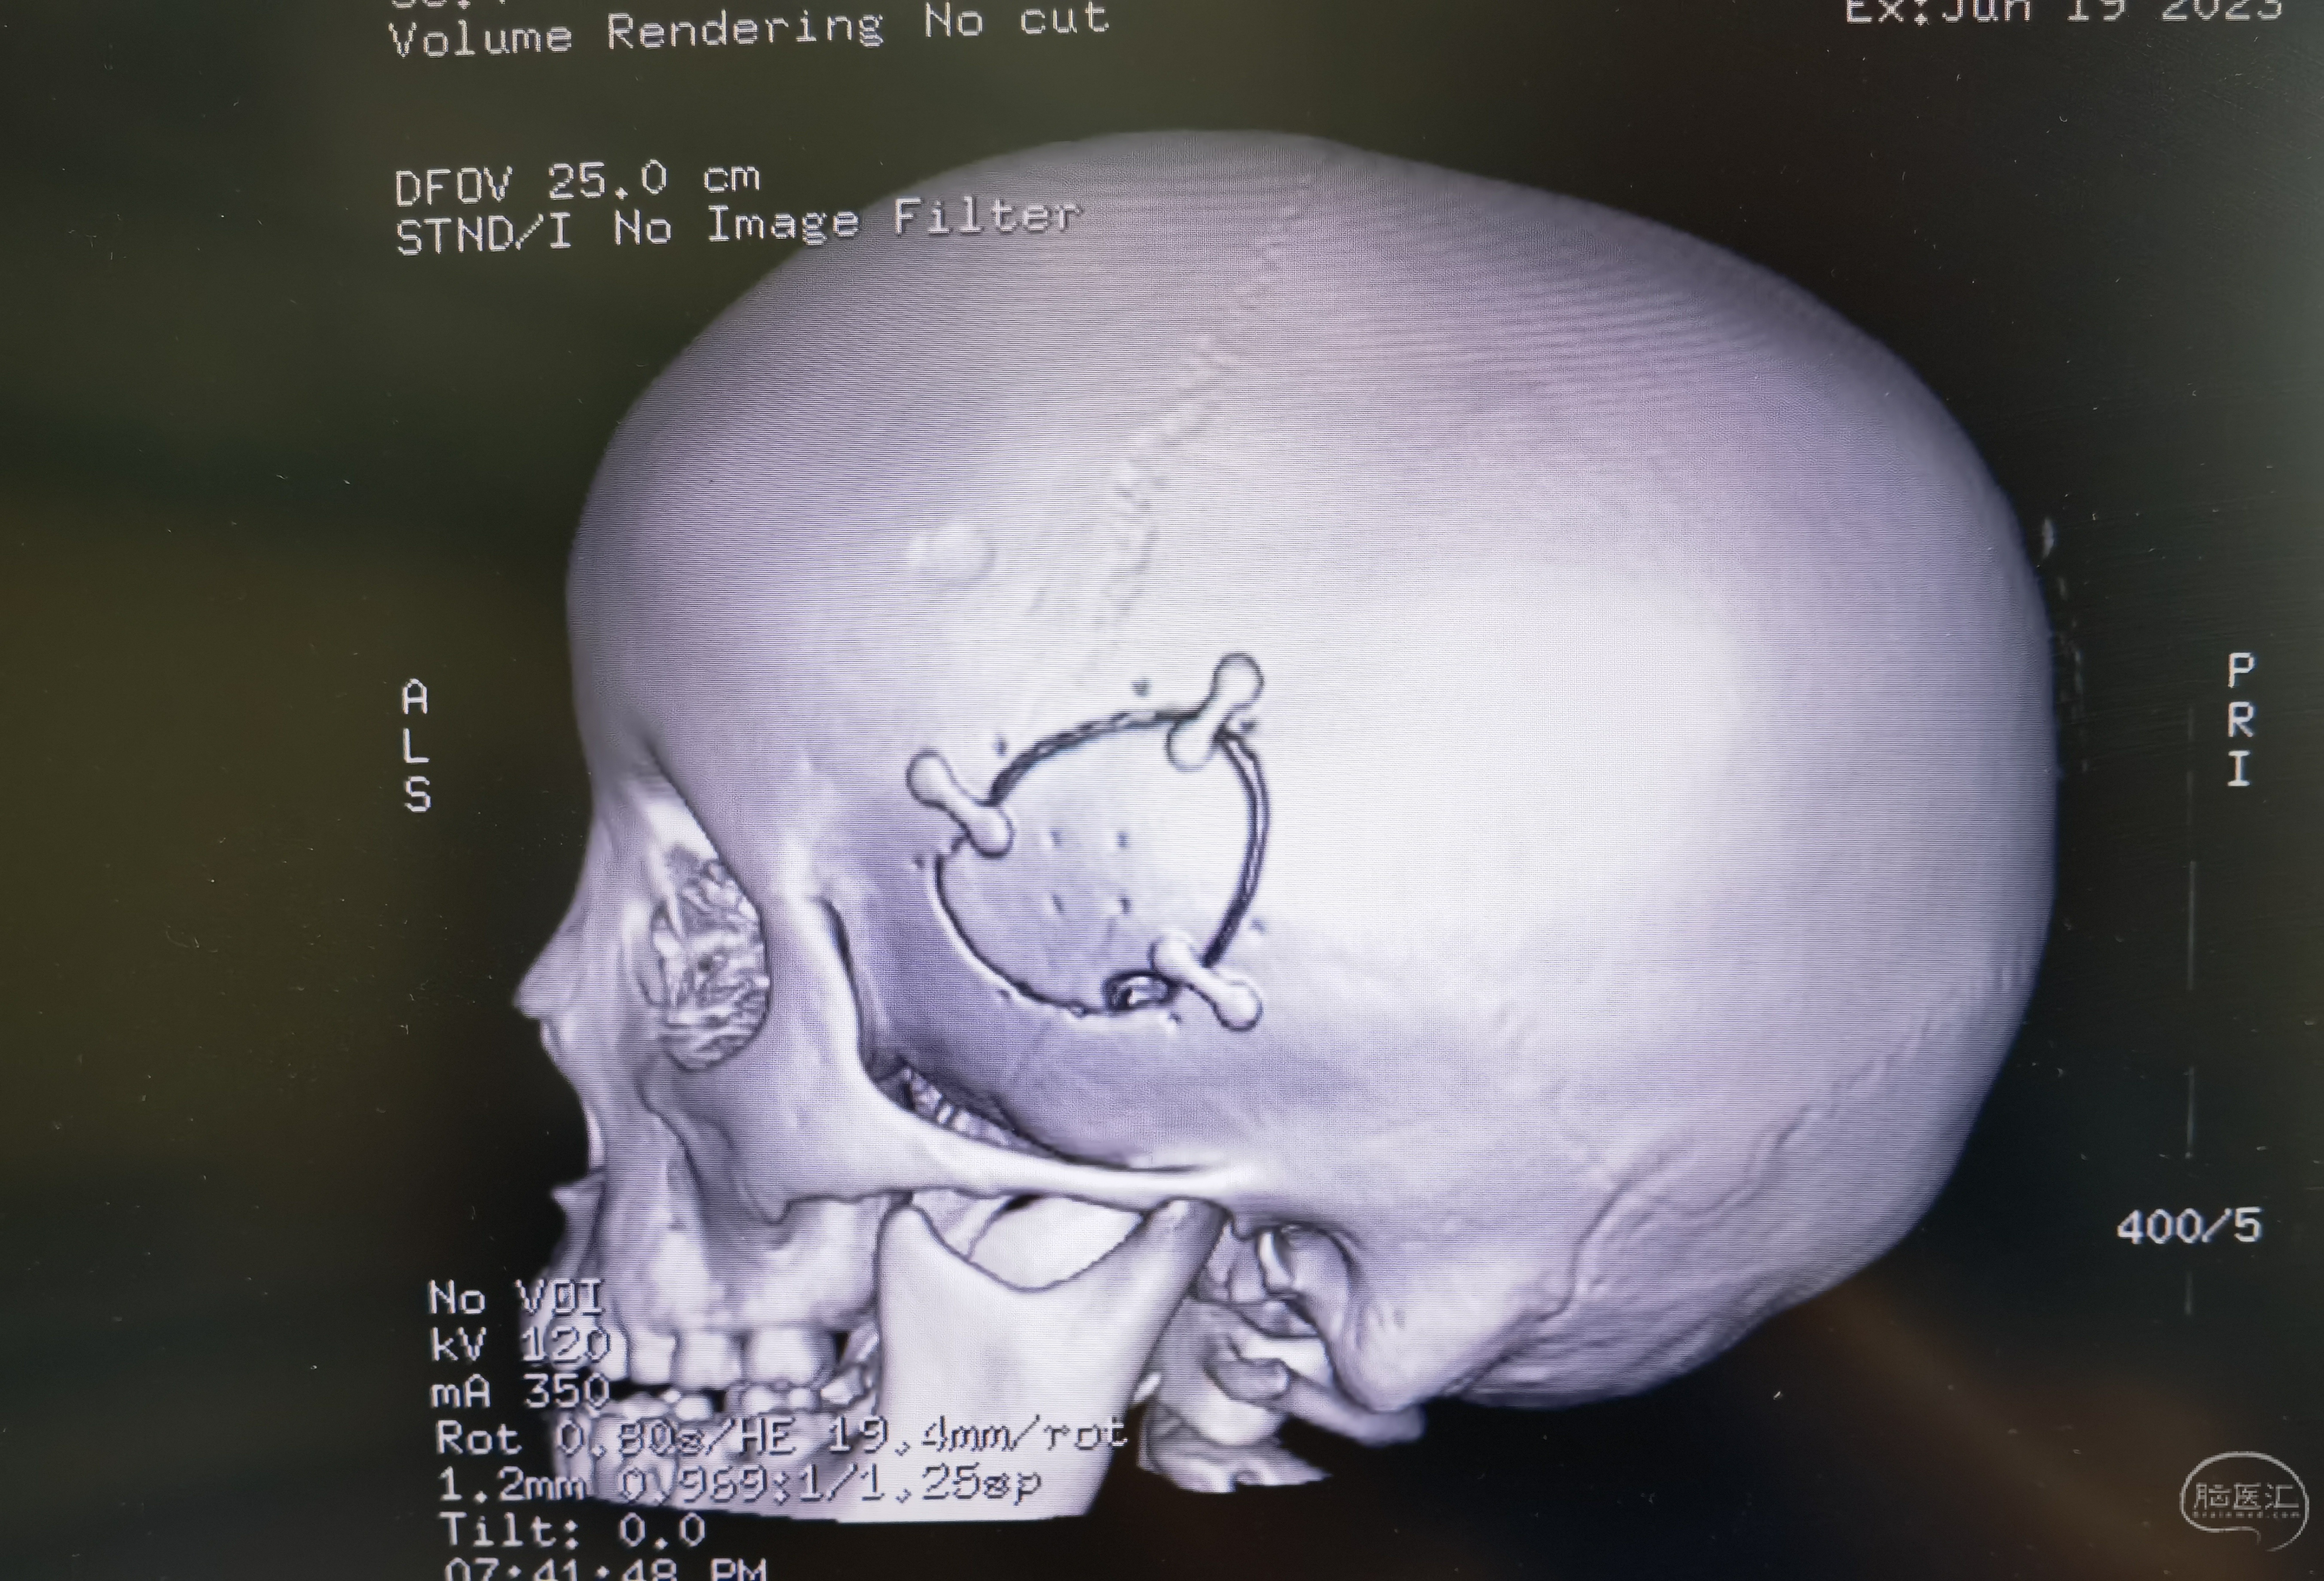

手术切口